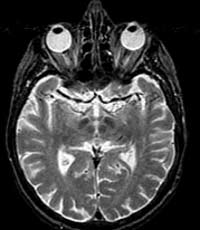

L'imagerie

par résonnance magnétique (IRM) L’avènement

de l’IRM à la fin des années 1970 a eu l’effet d’une

bombe dans le milieu médical. Cette nouvelle technique n’utilisait

ni les rayon X, ni les ultrasons, mais faisait plutôt appel aux champs magnétiques

en exploitant des propriétés physiques de la matière au niveau

sub-atomique, en particulier de l’eau qui constitue environ les trois quart

de la masse du corps humain. L’IRM, en plus d’une définition

supérieure au CT scan, permet aussi d’obtenir non seulement des coupes

axiales du cerveau comme le CT scan, mais aussi des coupes sagittales et coronales.